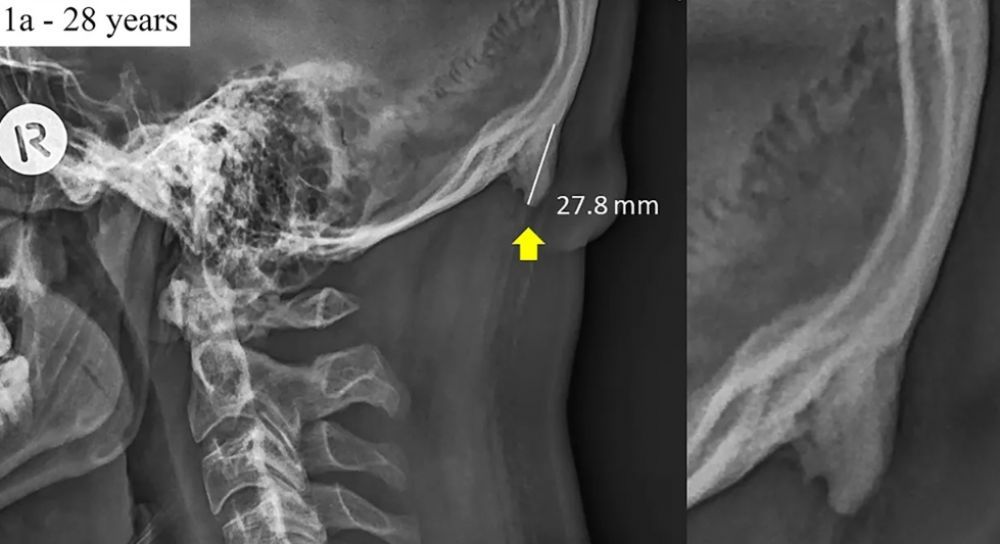

NUEVO HUESO EN EL CRANEO POR USAR SMARTPHONE

El uso de los smartphones ha causado algunos cambios en el cuerpo del ser humano. Ya se había señalado que el dedo pulgar de algunas personas estaba aumentando por escribir continuamente en los celulares, también se había advertido de problemas en la vista por el exceso de la pantalla móvil. Ahora científicos han descubierto que las personas están desarrollando un extraño hueso en la base del cráneo.

Según informa depor los más afectados por el nacimiento del extraño hueso, ubicado sobre el cuello, son los jóvenes. De acuerdo a los investigadores de la Universidad de Sunshine Coast, Australia, citados por Clarín, este hueso crece por la posición del ser humano cuando utiliza el celular.